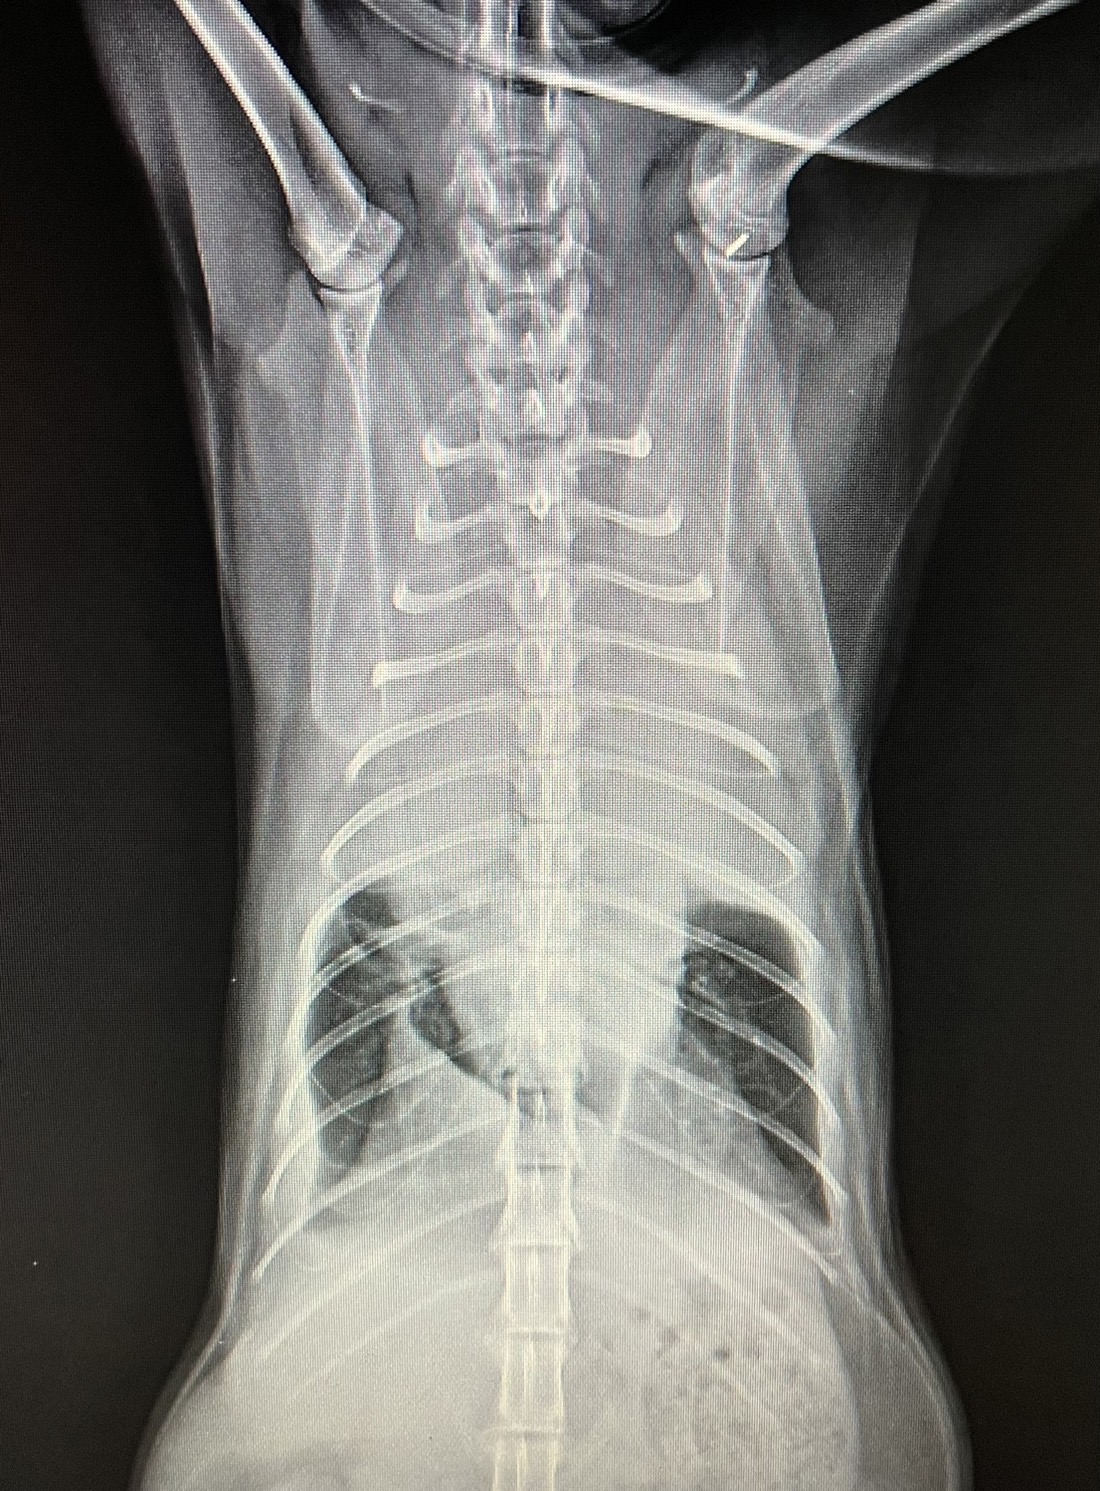

喉頭團塊 呼吸困難 急診

胸水

心包囊積液